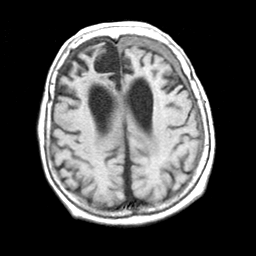

Pick's Disease, MR Study mr-t1 -- Slice #15

[Home][Help][Clinical] Slice 15